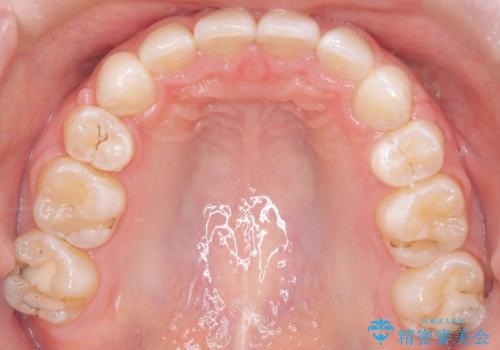

- 右上の八重歯と歯のデコボコ、そして上下の歯の中心(正中)のズレを気にされて来院されました。精密な検査の結果、歯が並ぶスペースが不足しているため、上顎の小臼歯(前から数えて4番目の歯)を抜歯し、そのスペースを利用して歯並び全体を整える治療計画を立案しました。これにより、八重歯の位置を適切に改善し、叢生(歯のデコボコ)を解消するとともに、上下の正中線のズレも改善することを目指します。

今回の矯正治療では、歯が並ぶスペースを確保するため、上顎の小臼歯を抜歯しました。抜歯によってできたスペースを有効活用し、ワイヤーやブラケットを使って右上の八重歯を適切な位置へ移動させ、叢生を解消していきました。また、治療を通じて上下の歯の中心である正中線のズレも改善するよう、慎重に歯を動かしました。治療の結果、長年気にされていた八重歯と歯のデコボコが解消され、上下の正中線も一致。機能的にも審美的にもバランスの取れた、美しい歯並びと笑顔を獲得していただけました。